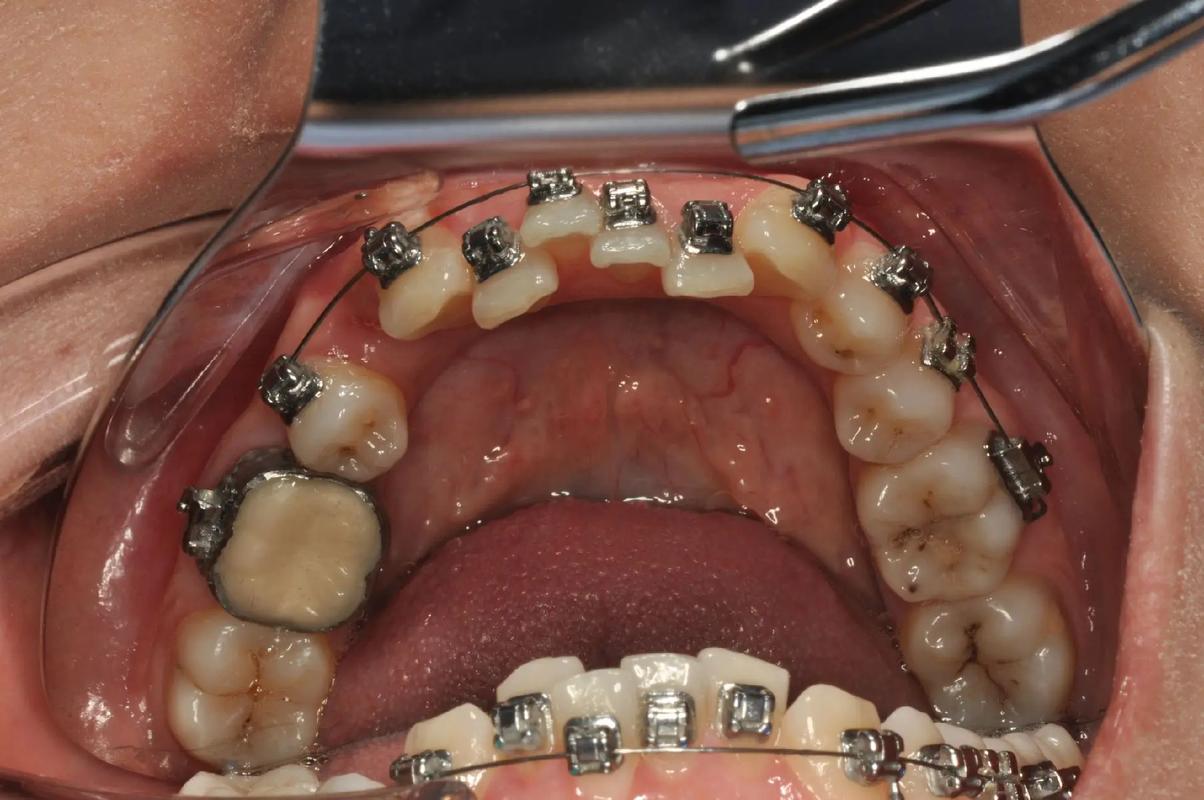

(图片来源网络,侵删)- 将选好的带环套在目标牙齿上,检查其就位情况。

- 检查要点:

- 就位度: 带环是否能顺利滑向牙齿颈部,到达最终位置?

- 密合度: 带环边缘是否与牙齿颈部紧密贴合?有无明显缝隙?

- 位置: 带环是否位于牙齿中央?有无颊舌向或近远中向的扭转?

- 咬合: 带环是否干扰咬合?是否导致早接触?

- 牙龈刺激: 带环边缘是否压迫或刺激牙龈?边缘是否光滑?